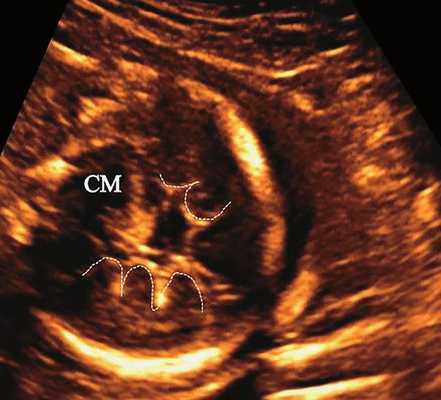

б) Представлен косой нижнеаксиальный 2D-срез. Пунктирная линия очерчивает выпуклые извилины с медиальной стороны височных долей (СМ - средний мозг).

| Набл. 2. 20,3 нед. | БПР - 21,5 нед. ОГ - 20,3 нед. Уплощенный затылок. Выпуклые темпоральные бугры (рис. 2а). Аномально повышенная бороздчатость и выпуклость извилин нижнемедиальной поверхности височных долей (рис. 2б). | Торакоабдоминальное соотношение - 63,3% (рис. 2в) Окружность груди - среднее для 18 нед. Длина ребра - среднее для 15 нед. | Бедренная кость 17,7% (61% от должной), изогнута ("телефонная трубка") (рис. 2г). Остальные кости - среднее для 13-14 нед. | Гипоплазия костей носа. |

В наблюдениях 1-3 наличие изогнутой бедренной кости (по типу "телефонной трубки") (рис. 1в, 2г, 3г) позволяло предположить наличие ТД I типа. Целе направ ленное исследование головного мозга этих плодов в дополнение к описанным скелетным признакам показало и картину ДВД. Была выявлена аномально повышенная бороздчатость и выпуклость извилин нижнемедиальной поверхности височных долей у плодов в наблюдениях 1-3 (рис. 1а, 2б, 3б). Это позволило установить диагноз ТД I типа.